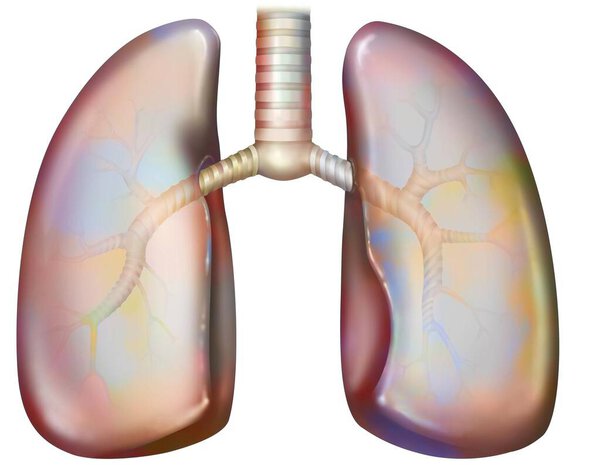

- Рак легких курильщика (с наличием депозитов смолы в бронхах).

Рак легких курильщика (с наличием депозитов смолы в бронхах).

Рак легких курильщика (с наличием депозитов смолы в бронхах).